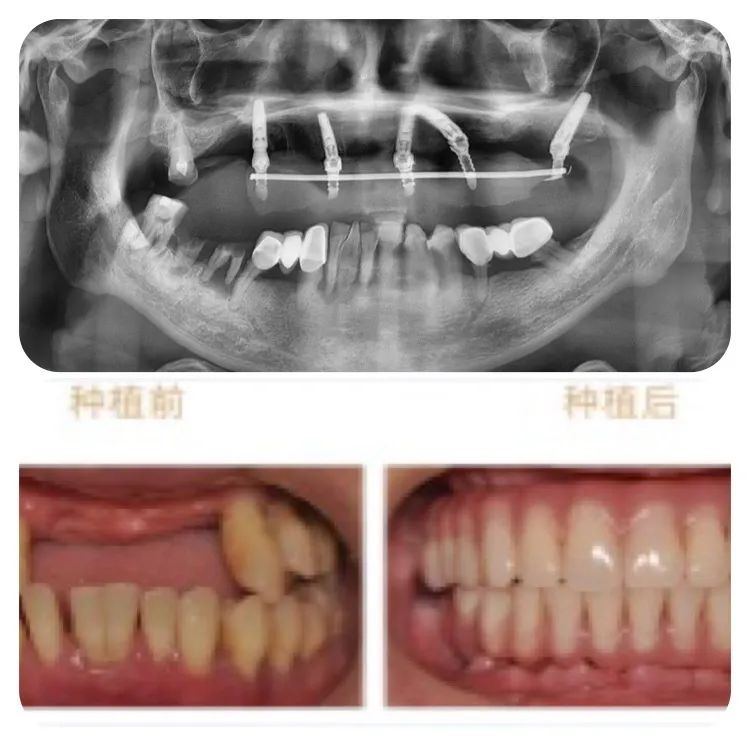

针对老人的口腔条件,重庆泰康拜博口腔VIP种植工作室通过3D数字化种植设计系统为他个性化计了带1颗穿翼板种植的即刻负重种植牙方案,即拔即种,全口牙在1天之内完成了种牙、戴冠全过程,手术完成后带上临时牙冠,牙齿就已经可以正常使用。

术后1周复查,通过口腔CT检查,可以看见老人的种植牙非常精准、稳固。老人自己也描述,他在种牙的时候感觉非常轻松快速,几乎没有痛感,打个盹的功夫,牙齿就种好了。